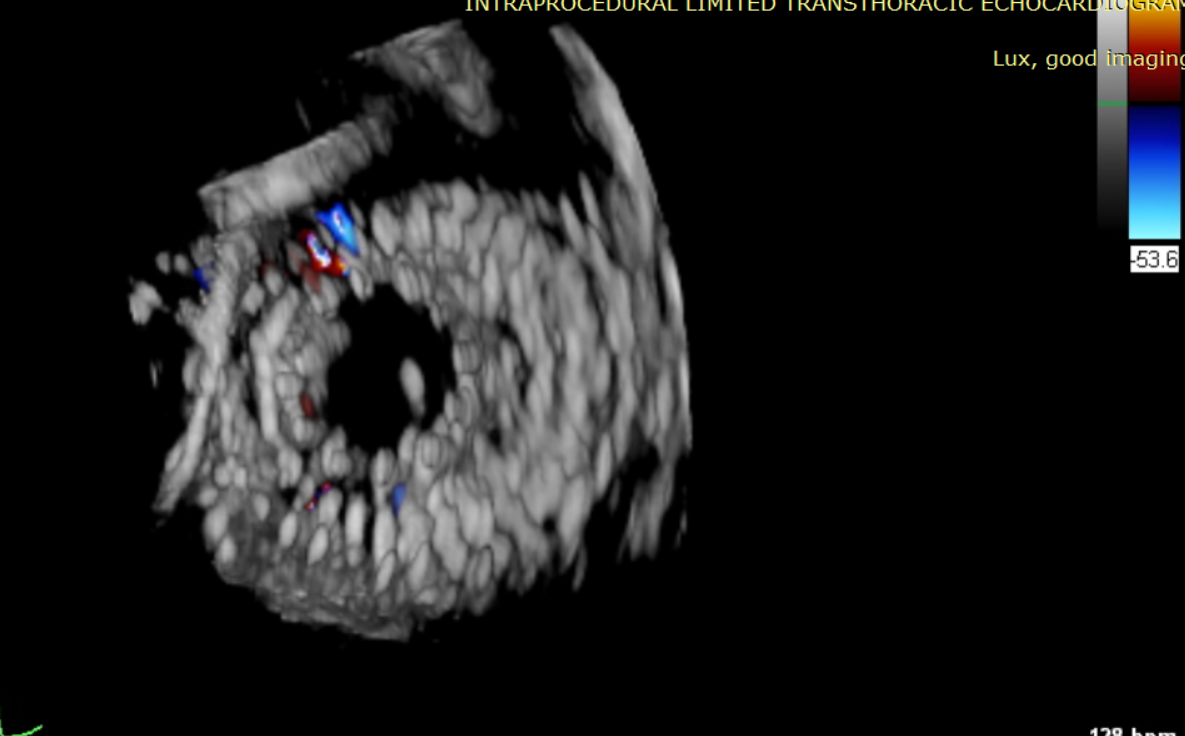

術中輸送器在超聲引導下調整位置

術后超聲提示僅殘余輕微瓣周漏